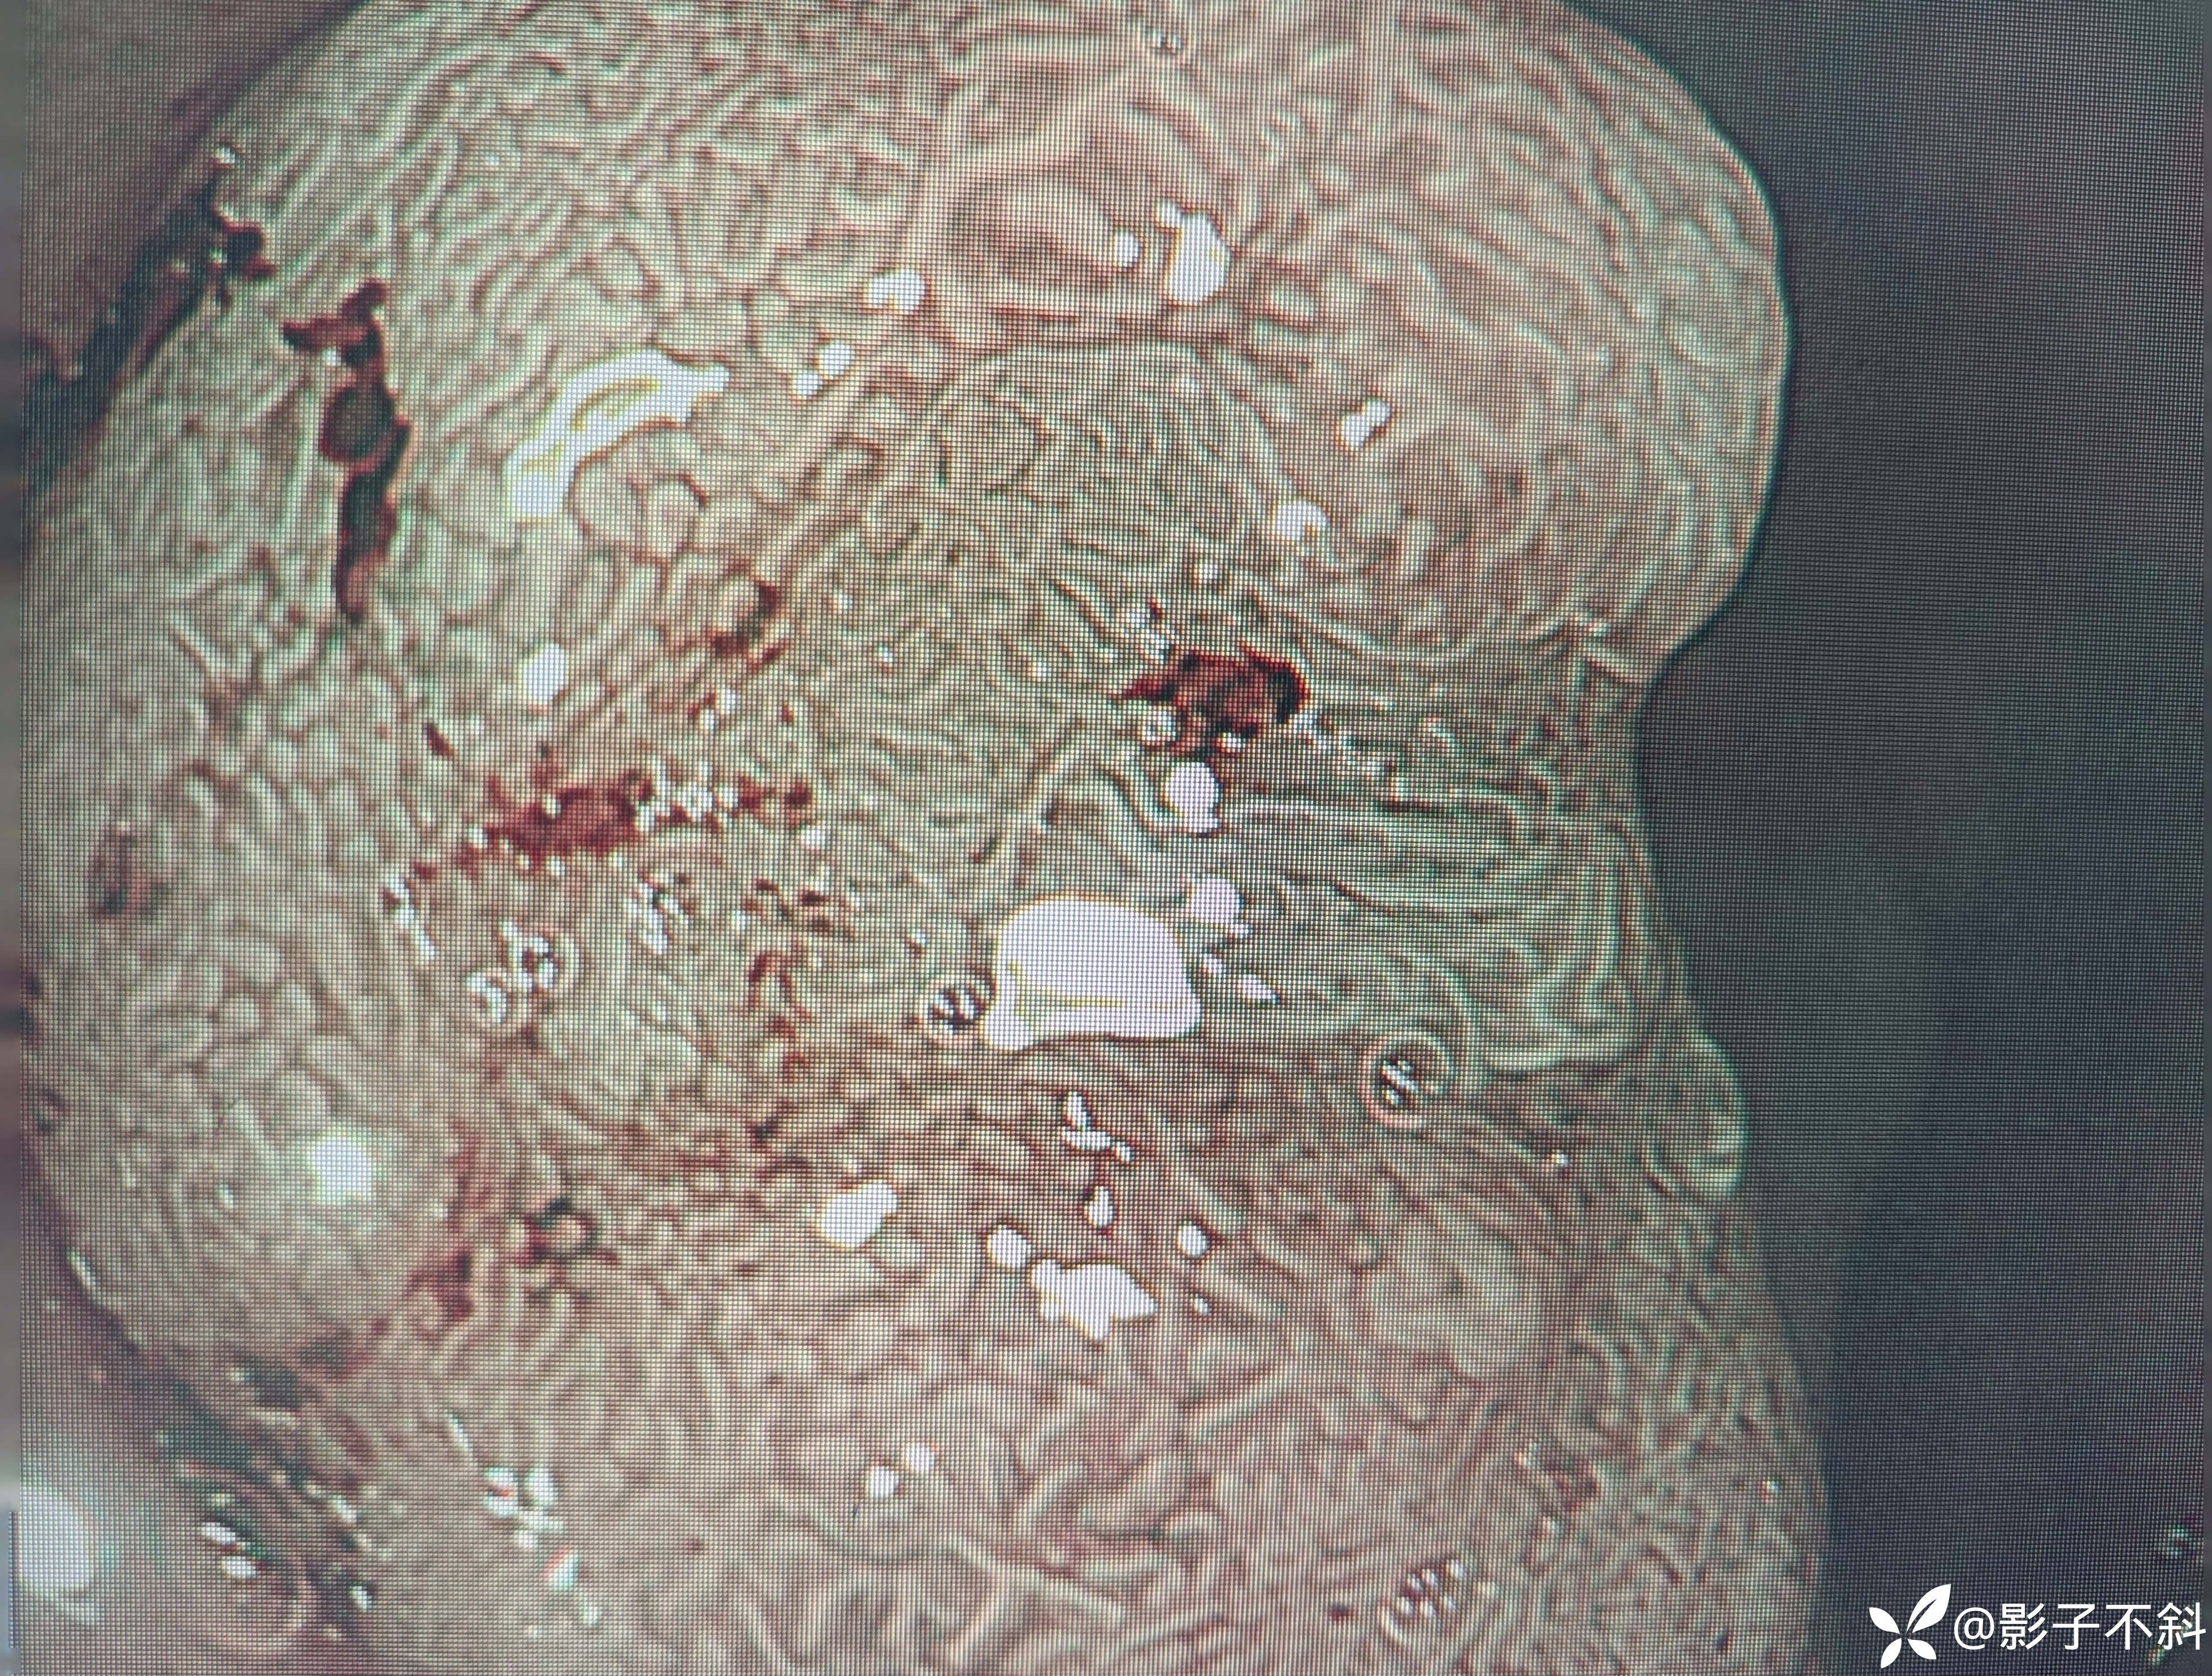

直肠见如下病变

处理分析

EMR